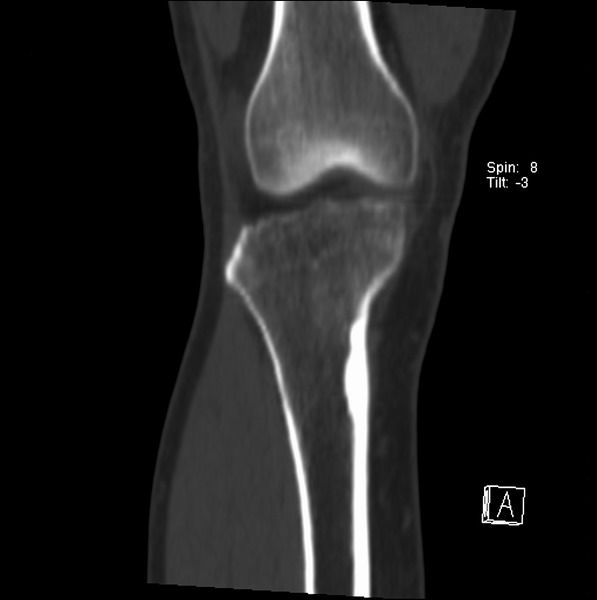

右侧膝关节疼痛一月

男、48

股骨下段、胫骨上段。

1、股骨干骺端病变考虑干骺端纤维性皮质缺损愈后(非骨化性纤维瘤)改变,胫骨近端内生骨瘤(或干骺端纤维性皮质缺损愈后改变);

2、骨关节炎,骨质增生,股骨外侧髁退变性囊肿(关节面软骨下囊肿);

1、股骨干骺端病变考虑干骺端纤维性皮质缺损愈后(非骨化性纤维瘤)改变,胫骨近端内生骨瘤;

股骨干骺端病变考虑非骨化性纤维瘤。